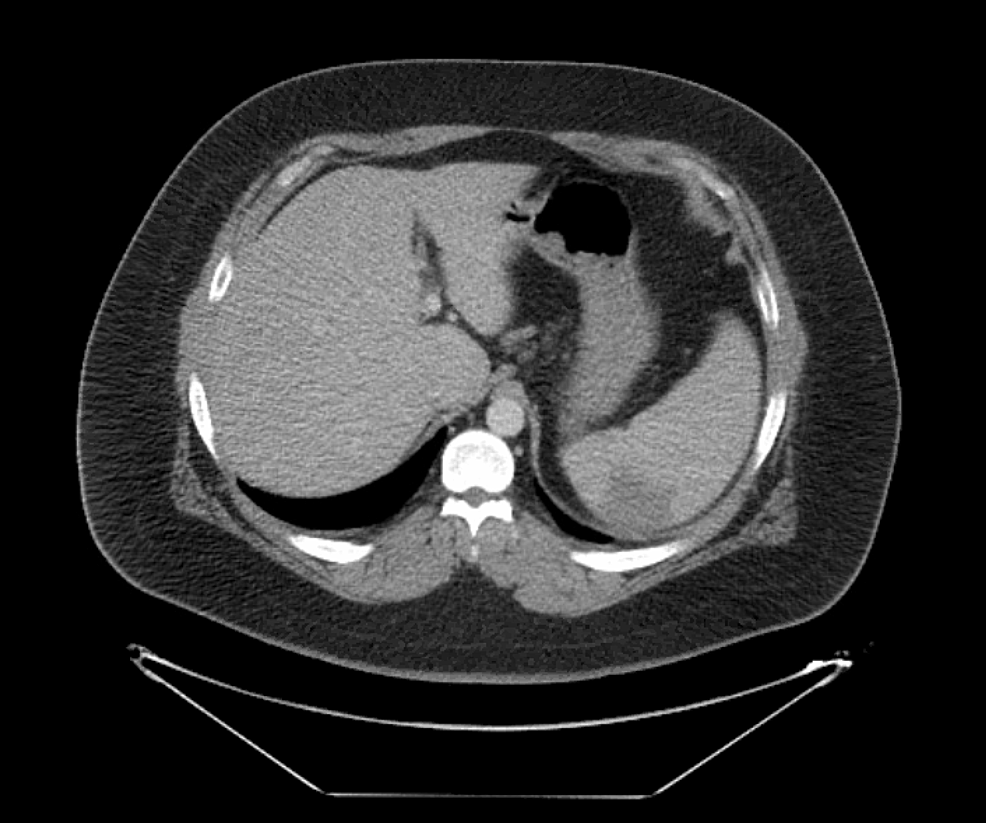

From radiologykey.com

Splenomegaly and Hypersplenism Radiology Key How Common Is An Enlarged Spleen With Mono An enlarged spleen occurs in up to 50% of those with mono. Mononucleosis may cause enlargement of the spleen. An enlarged spleen that ruptures (bursts) is the biggest concern with mono in previously healthy people. If your spleen bursts, it. We’ll also cover how to identify and treat mono, which should also help. A blow to the abdomen could cause. How Common Is An Enlarged Spleen With Mono.